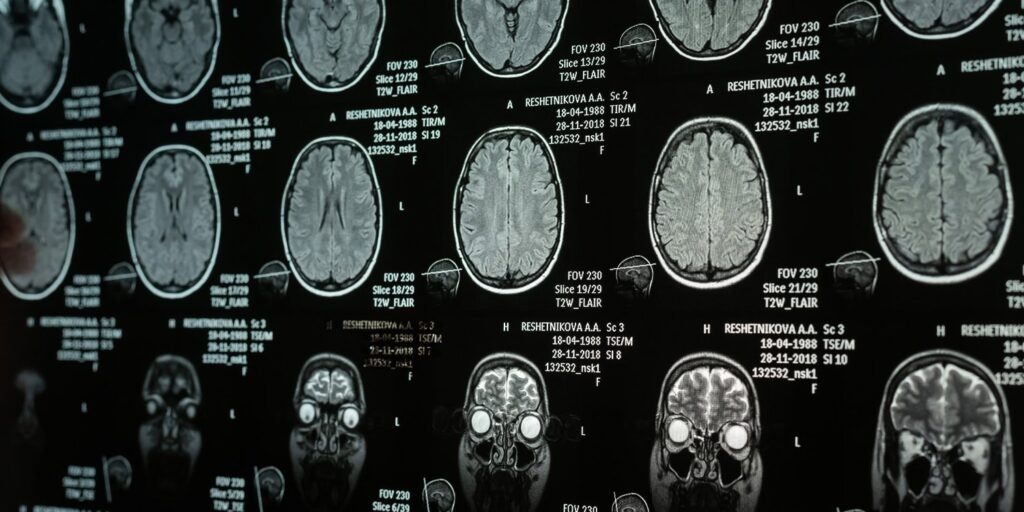

The researchers then analyzed the participants’ brains using a high-resolution magnetic resonance imaging scanner. They utilized specialized software to measure various structural aspects of the anterior insula. These measurements include the total volume of gray matter in the area and the degree of gyrification. Volume usually reflects the number of neurons and supporting cells at a particular location. Gyration refers to the degree of folding of the surface of the brain, which allows a larger cortical surface area to fit inside the skull.

Brain folding occurs early in human development. Because of this timeline, the degree of brain rotation is thought to be an indicator of how the brain was formed early in life, rather than a characteristic that changes dramatically from day to day. To understand the relationship between brain anatomy, emotion regulation, and narcissism, the researchers ran a statistical mediation model.

Brain scans revealed a negative association between narcissistic traits and anterior insula size. Those who scored higher on both grandiose and vulnerable narcissism scales tended to have slightly smaller right anterior insula volumes. In the case of vulnerable narcissists, this negative relationship also extended to the left anterior insula.

Mediation analysis added nuance to these negative anatomical correlations. The researchers found that expressive suppression habits were statistically involved in the relationship between right anterior insula volume and narcissistic vulnerability. It also mediated the relationship between right insular surface folding and both spectacular and fragile features.

The statistical model also worked the other way. Narcissistic traits mediated the relationship between both left and right anterior insula volume and the use of expressive suppression. This illustrates a three-way dynamic in which the tendency to hide emotions forms a link between brain anatomy and personality, while personality simultaneously forms a link between emotional habits and brain structure.